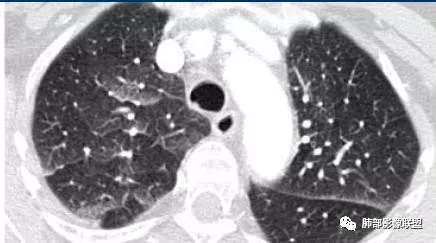

一切∮随缘:双肺多发斑片状渗出影,边界模糊,部分周围可见正常肺组织,其内可见血管走行自然,支气管无明显改变,病变整体以中内带为主,胸膜下受累不明显。

中年男性,呼吸困难为主。两肺弥漫性GGO,上肺内夹杂小囊。胸膜下累及少,未见明显小叶间隔增厚,两下肺可见小叶内间隔增呈小网格征,左下肺可见索条灶,急性感染临床不符合,第一想到了PCP,中期,所以需要查 HIV。第二肺水肿,但是两肺门不是对称,小叶间隔增厚几乎看不到,所以不考虑。第三过敏性肺炎,肺泡改变?第四滤泡性细支气管炎。第五弥漫性肺泡损伤,药物性?但没有特殊用药病史所以排除。综上还是考虑PCP可能大些。

中年男性,呼吸困难为主,胸部CT双肺由内向外分布为主的磨玻璃影,考虑pjp,鉴别HP,肺水肿。

两肺弥漫性磨玻璃,上肺内夹杂小囊,胸膜下未见累及,中年大叔,考虑PCP,查 HIV。

双肺向心性磨玻璃影,似看见小气囊,首先考虑PJP,查HIV抗体,鉴别CHP,看看外周血嗜酸粒细胞是否高。

中年男性,呼吸困难为主,两肺弥漫性磨玻璃,夹杂小囊腔,肺门向外外分布,月弓征,建议临床排查pcp,鉴别hp

大雄:中年男性,呼吸困难4月余,其他无异常。影像学表现双肺弥漫磨玻璃影,中上肺及中内带分布为主,伴下肺少许纤维化。第一印象比较符合PCP,但是病史四个月不伴有发热及干咳,似乎可能性不大。影像学还需要考虑的有HP,PAP,药损,EP。HP和药损需要病史支持,询问有无环境暴露以及药物相关因素。AEP从病史可以排除,CEP没有嗜酸增高,也基本排除。PAP影像学不太典型,但临床符合,可以放鉴别诊断剩下的DAD和DAH基本不用考虑了,病史不支持。再有就是慢性肺水肿,需要有临床的诱因。

晨读结果:患者HIV阳性,胸部CT诊断PCP。患者转上级医院治疗,电话随访,按PCP治疗,病变明显吸收,后出院。

中期:孢子菌在肺泡腔内大量繁殖,引起炎性渗出及肺泡上皮增生,肺泡液内含有滋养体的嗜酸性渗出物及纤维蛋白和脱落的上皮细胞,Ⅱ型肺泡上皮细胞增殖修复受损的肺泡毛细血管间膜,肺间质内巨噬细胞、浆细胞和淋巴细胞增殖导致间质性肺炎,就是说有肺泡腔的密度增高,也有间质的增厚,整个肺受累区域密度都增高,形成以肺门为中心双侧对称的弥漫性磨玻璃样改变,胸膜下较少累及,呈典型的月弓征,采用积极的对症治疗后,大多数病变可吸收消失。

注意肺孢子菌肺炎的肺部影像看上去比较“干”,不会呈现重力趋势。肺血管影及支气管影都比较清楚,尤其是含气支气管影,常常会衬托得格外清晰。

1、双肺从中心向外周对称性弥漫分布的磨玻璃密度影,无重力分布特点

2、中内带分布为主,胸膜下较少受累,可见月弓征

3、下肺纤维灶形成

结合患者症状典型的呼吸困难症状及影像学改变,临床症状轻,影像重,双肺从中心向外周对称性弥漫分布的磨玻璃影,无重力分布,胸膜下受累不明显(月弓征),呈典型的间质性改变,需要考虑肺孢子菌肺炎的可能,临床上需要结合有无HIV、使用免疫抑制剂病史、器官移植等免疫缺陷病史,还可以借助化验CD4细胞、LDH等进一步判断病情。